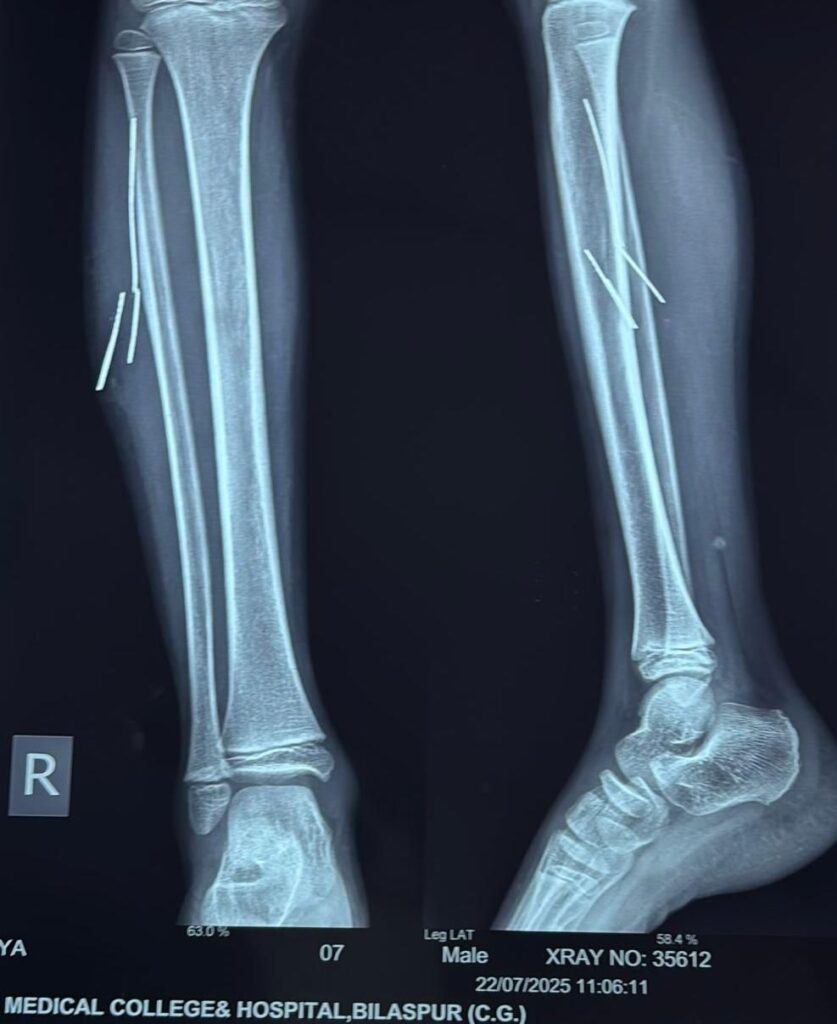

लमेर निवासी 10 वर्षीय आदित्य खांडे पिता दीप कुमार लगभग चार माह पूर्व साइकिल चलाते समय दुर्घटनाग्रस्त हो गया था! हादसे में साइकिल का टायर फटने से बाहर निकला लोहे का तार उसके दाहिने पैर में घुस गया! तार पैर में टूटकर अंदर फंस गया और चार टुकड़ों में लगभग 2 से 5 सेमी लंबाई में मांसपेशियों में धंस गया! इसके बाद बच्चे को लगातार सूजन और दर्द की शिकायत बनी रही!

तीन दिन पूर्व परिजन उसे सिम्स के सर्जरी विभाग में लेकर पहुंचे, जहां सर्जन डॉ. बी.डी. तिवारी ने जाँच करवाई! एक्सरे और सोनोग्राफी से यह पुष्टि हुई कि तार पैर की मांसपेशियों में गहराई तक धंसा हुआ है! और अंदर ही अंदर मवाद बन चुका है!

स्थिति की गंभीरता को देखते हुए डॉ. ओ.पी. राज एवं डॉ. बी.डी. तिवारी ने ऑपरेशन का निर्णय लिया! परंतु ऑपरेशन के दौरान चीरफाड़ को न्यूनतम रखने और तारों की सटीक जगह जानने के लिए रेडियोलॉजी विभाग की मदद ली गई! विभागाध्यक्ष डॉ. अर्चना सिंह के निर्देशन में असिस्टेंट प्रोफेसर डॉ. अमन अग्रवाल ने ऑपरेशन थिएटर में ही लाइव सोनोग्राफी के माध्यम से लोहे के तारों की सटीक स्थिति चिन्हित की! इसके आधार पर सर्जनों ने बहुत ही कम चीरफाड़ कर सफलतापूर्वक सभी चारो तारों को निकाल दिया गाया मेल सर्जरी वर्ड मे इलाज जारी है!